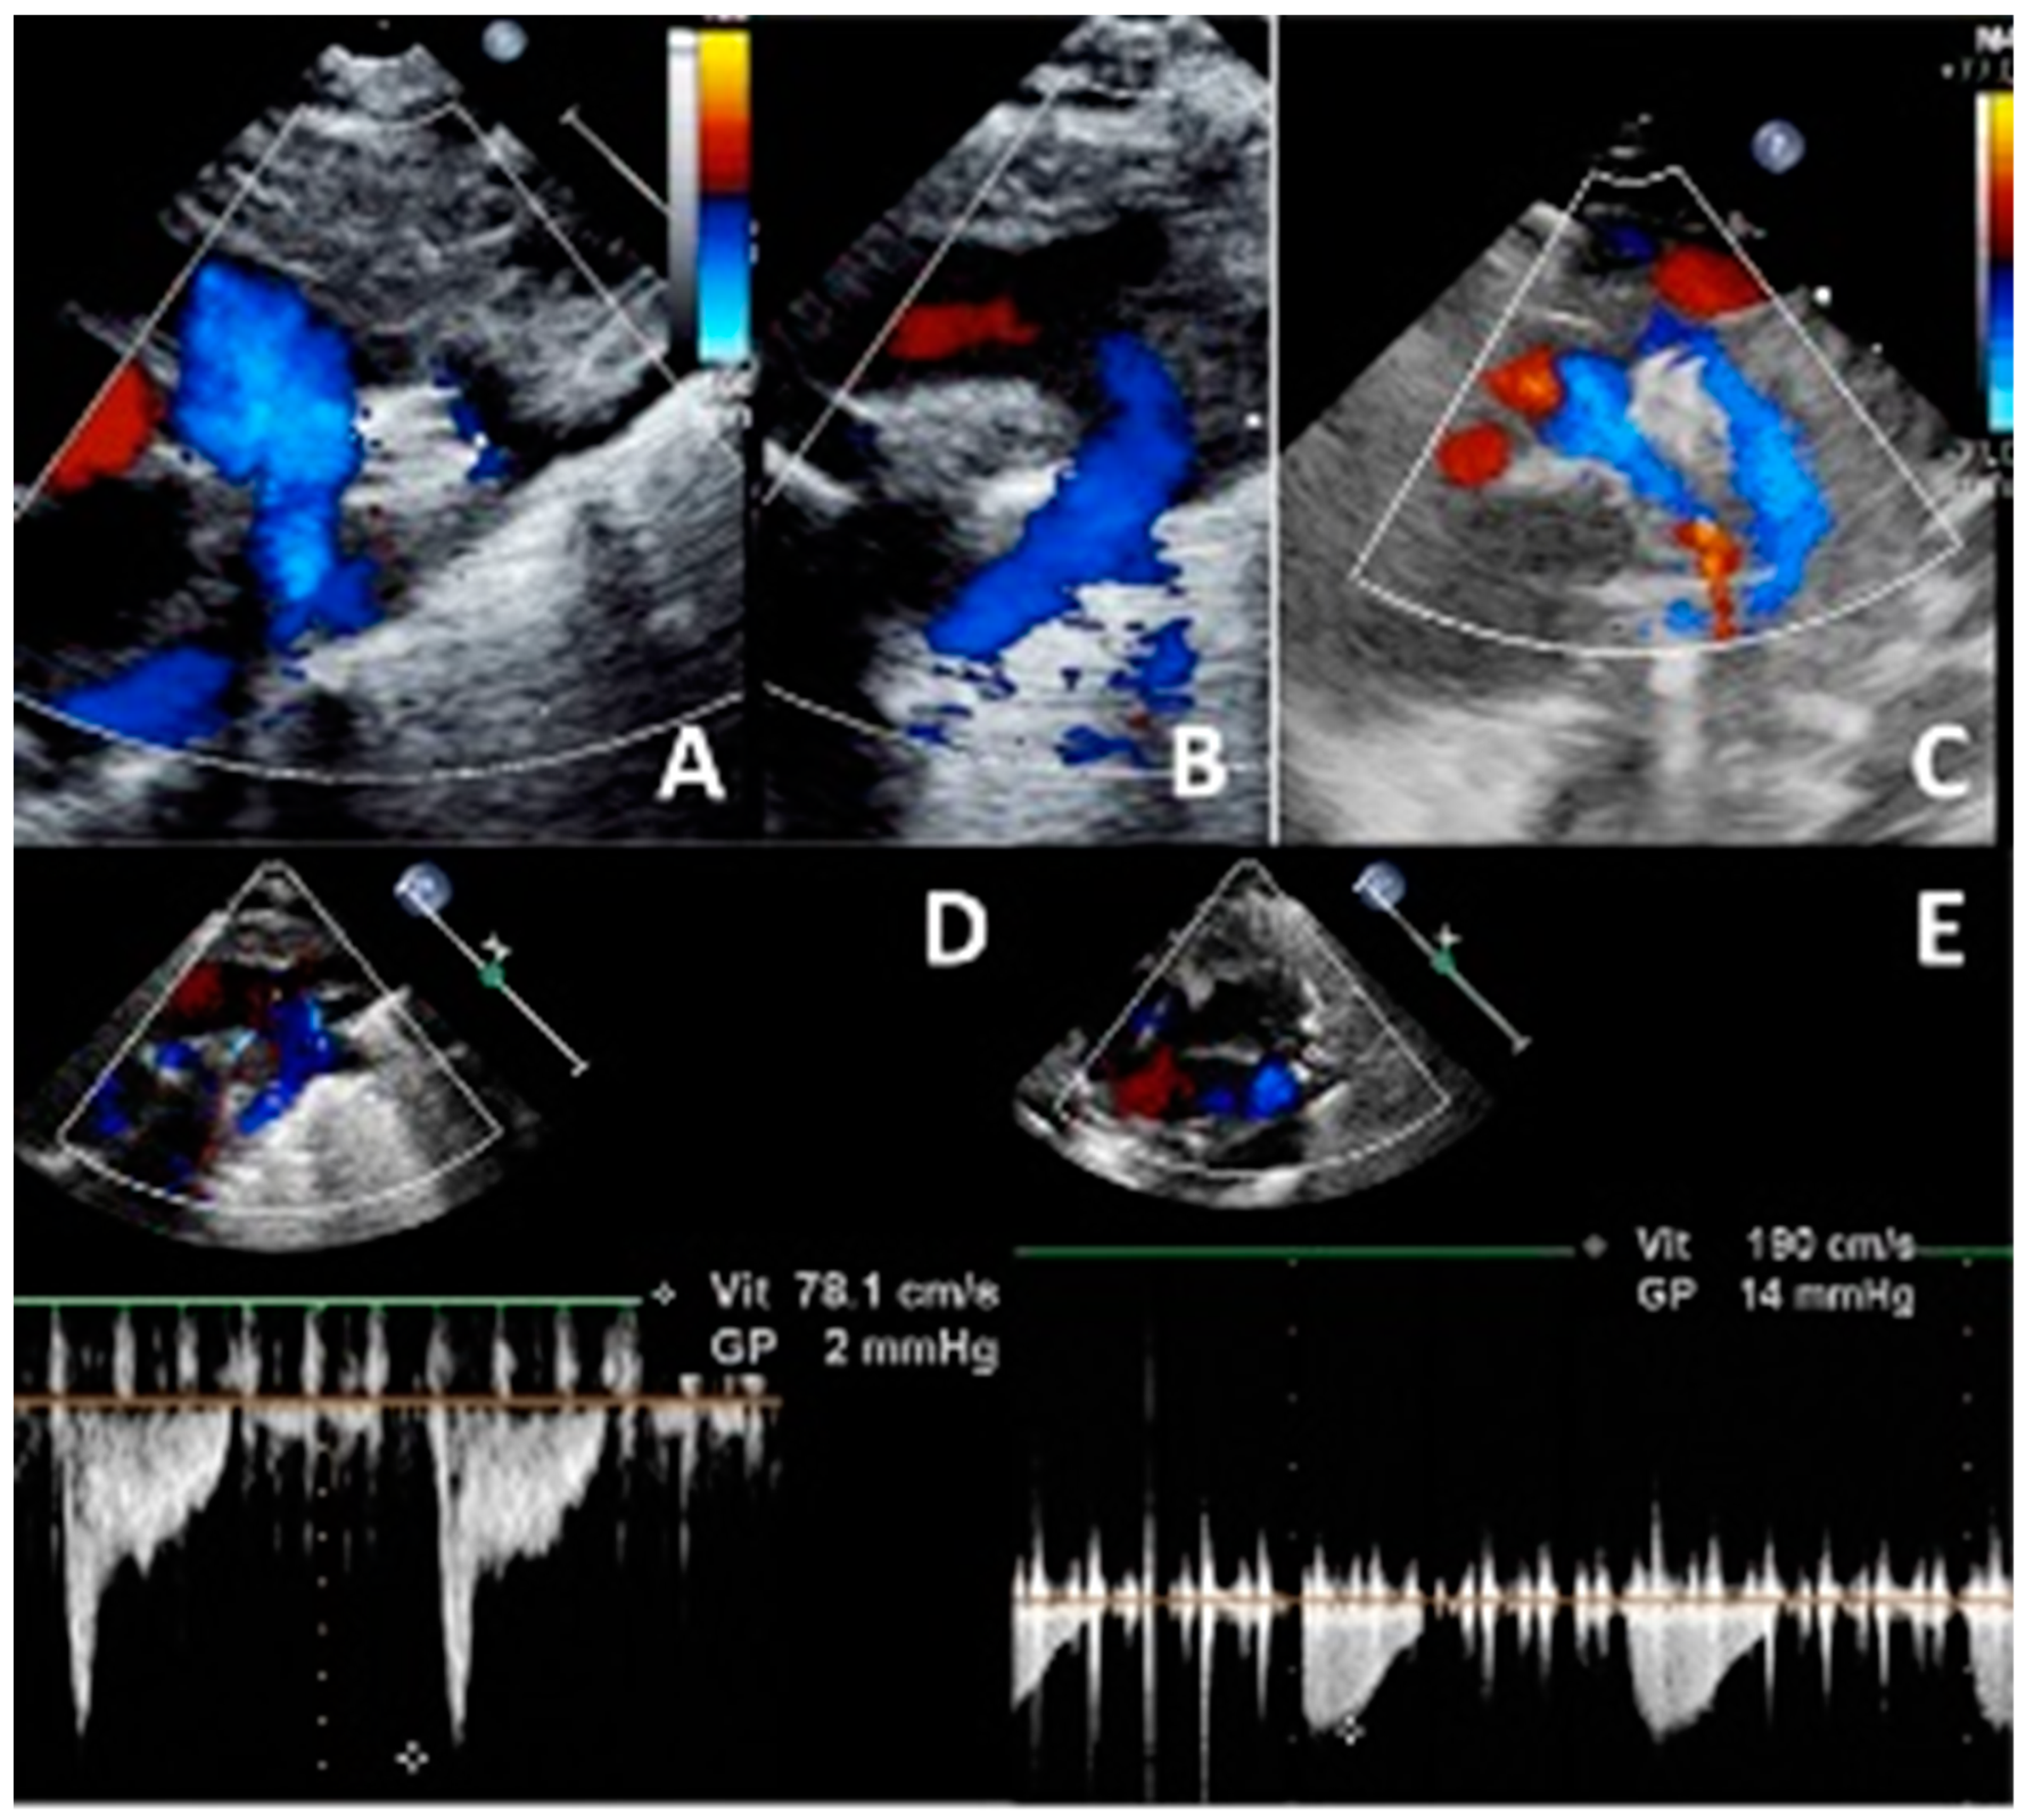

- Meot, M.; Gaudin, R.; Szezepanski, I.; Bajolle, F.; Bonnet, D.; Malekzadeh-Milani, S. Transcatheter patent arterial duct closure in premature infants: A new technique to ease access to the patent arterial duct, with particular benefit for the tricuspid valve. Arch. Cardiovasc. Dis. 2021, 114, 482–489. [Google Scholar] [CrossRef]